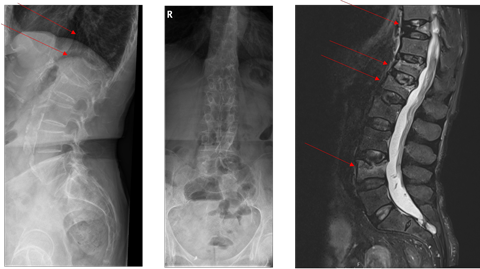

Röntgen LWS + MRT LWS:

Bei der Patientin liegt einerseits eine hochgradig reduzierte Knochenmineraldichte vor im Sinne einer sekundären manifesten Osteoporose mit multiplen atraumatischen Wirbelkörperfrakturen und andererseits zusätzlich eine

Osteomalazie. Die Ursache der Osteomalazie liegt in der Malabsorption, trotz hochdosierter Vitamin D Substitution liegt ein Mangel vor. Zudem wird zu wenig Calcium über den Gastrointestinaltrakt aufgenommen. Konsekutiv erhöht sich